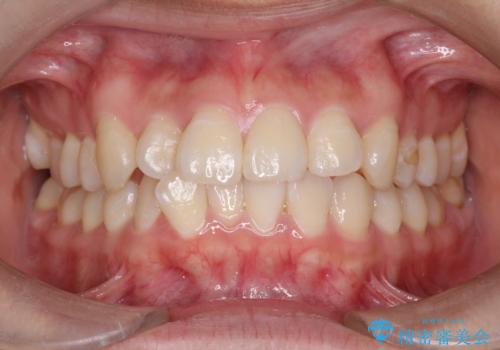

審美装置を用いたワイヤー矯正|非抜歯で歯の凸凹を改善

- 患者様は**歯の凸凹(叢生)**を気にされて来院されました。診査の結果、歯列のスペースが不足しているものの、抜歯をせずに改善できる状態でした。そこで、目立ちにくい審美装置(白いブラケットとホワイトワイヤー)を使用したワイヤー矯正を提案しました。歯列のアーチを広げながら、適宜IPR(歯の幅をわずかに調整する処置)を行い、非抜歯で自然な歯並びへと導く計画を立てました。

治療では、白いブラケットとホワイトワイヤーを使用し、矯正装置が目立ちにくいよう配慮しました。歯列を拡大しながら適切に歯を移動させ、IPRを併用することで、無理なくスペースを確保しました。見た目に配慮しながら、歯の凸凹をスムーズに整え、噛み合わせも改善。患者様からは「装置が思ったより目立たず、歯並びがきれいになって嬉しい」との声をいただきました。